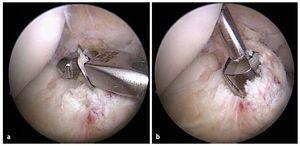

Fig. 10 a) El gancho de la guía se desplaza por detrás de la línea inter-condílea. b) A continuación se perfora el alambre guía (2,4 mm) en el centro de la inserción del ligamento cruzado anterior.

Fig. 11 La guía se extrae y se controla la posición del agujero remanente insertando el artroscopio dentro de la articulación a través del portal medial. Línea negra: línea intercondílea; línea punteada negra: interfaz huesocartílago; línea punteada roja: zona de inserción. AM: inserción del haz AM; PL: inserción del haz PL.